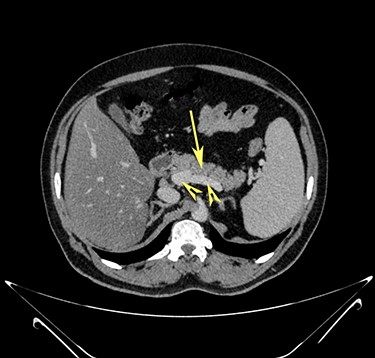

Transverse section image of a contrast-enhanced CT scan of the abdomen at level 2–2 (Fig. 1), showing the pancreas’ normal head and body (long arrow). The confluence of the splenic vein and portal vein are labelled using arrowheads.